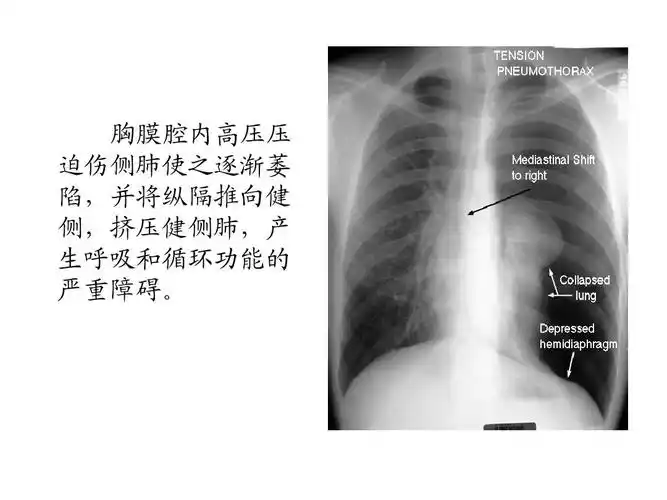

气胸的x线表现

气胸读片要点

x线诊断要点丨气胸胸膜及胸壁病变